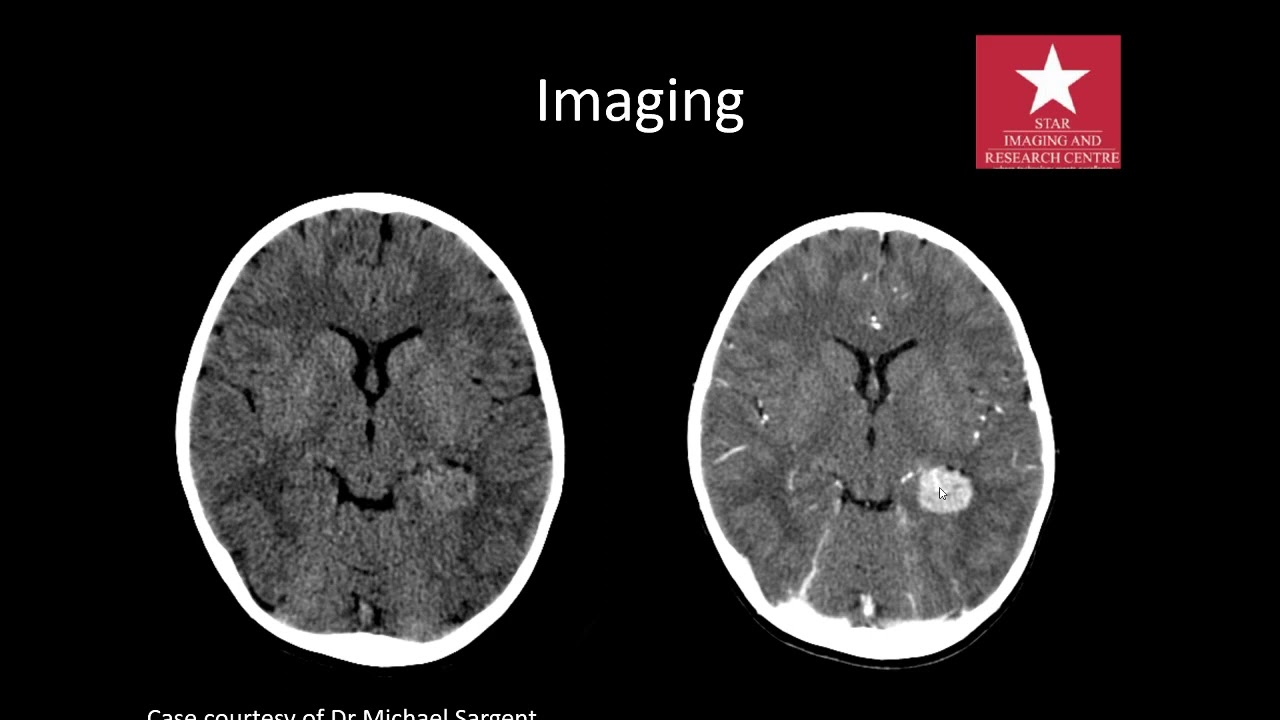

imaging of Intraventricular tumours